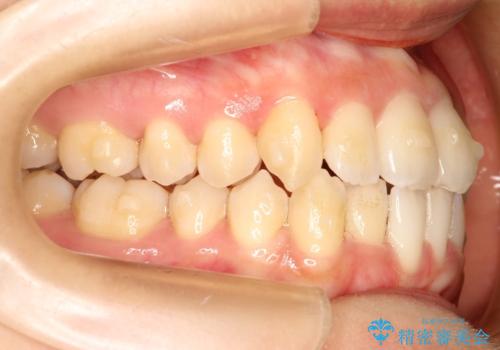

- 前歯の歯並びの改善を希望され来院された患者様です。

初診時の歯並びの状態としては、上下ともに全体に及ぶの中等度以上のがたつき(叢生)があり、前歯数本が反対交合の状態でした。

強い叢生がありましたが、抜歯は行わず上下顎ともに、主に歯列弓の拡大とディスキング(歯と歯の間に隙間を作る処置)を行い叢生を改善しました。